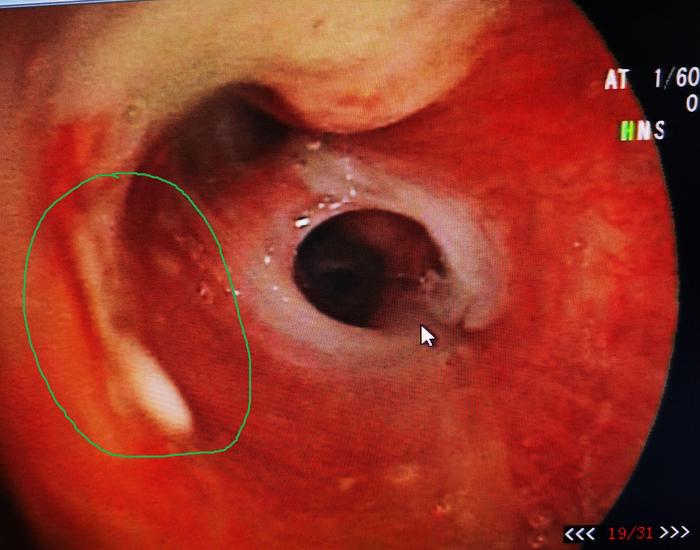

于是我们换4.0mm直径的细支气管镜进入该支气管亚段再次检查,发现左上叶上舌段亚段内白色坏死物,为了进一步确诊,我们给予钳检。

图2

钳检病理回报见真菌孢子及菌丝样物,故该患者实际上不是细菌感染,而是曲霉菌感染所致,治疗上予注射用伏立康唑(0.2g,每日2次)治疗。50天后复查支气管镜,原病灶处明显好转,气管镜下予伏立康唑局部注射治疗。